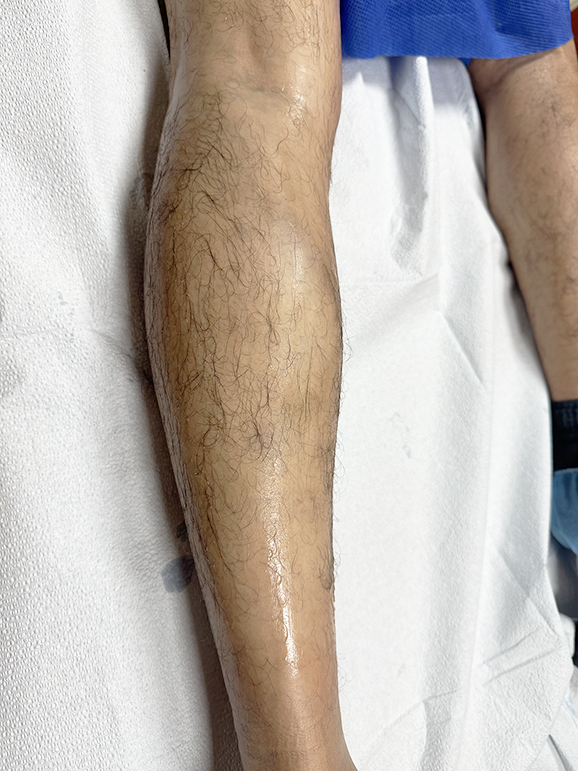

Venous Ulcer after failed skin graft

Case ID: 3991

Longstanding venous ulcer of many years that failed compression therapy, serial debridements, and recently split thickness skin grafting. Patient had axial short saphenous vein insufficiency with associated varicosities underneath wound bed. Underwent microfoam sclerotherapy of refluxing truncal and accessory veins with several applications of skin subsitute grafts and…